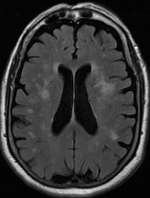

Leukoaraiosis[1] or white matter hyperintensities (WMHs)[2] are the nonspecific hyperintense changes in the cerebral white matter frequently seen on CT and MRI in aged individuals and even young adults sometimes.[3] It is a condition routinely found in elderly people.

The term leukoaraiosis was coined in 1986[4][5] by Hachinski, Potter, and Merskey as a descriptive term for rarefaction ("araiosis") of the white matter, showing up as decreased density on CT and increased signal intensity on T2/FLAIR sequences (white matter hyperintensities) performed as part of MRI brain scans.

These white matter changes are also commonly referred to as periventricular white matter disease, or white matter hyperintensities (WMH) due to their bright white appearance on T2 MRI scans. Many patients can have leukoaraiosis without any associated clinical abnormality. However, underlying vascular mechanisms are suspected to be the cause of the imaging findings. Hypertension, smoking, diabetes,[6] hyperhomocysteinemia, and heart disease are all risk factors for leukoaraiosis.